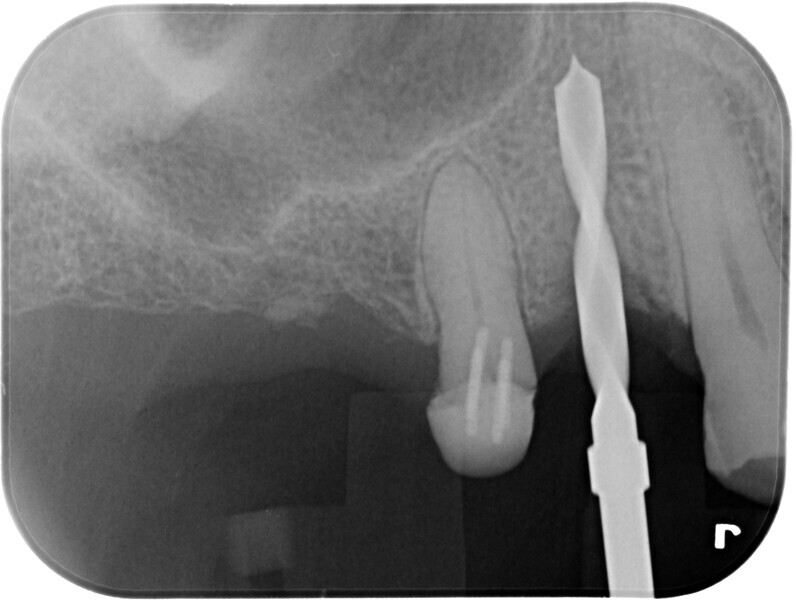

Fig. 3: Initial periapical radiograph.

Two months after tooth #14 had been extracted, a CBCT scan (GO, NewTom) and intra-oral scan (Medit i700 wireless) were performed, and the two data sets were merged on 3Shape Implant Studio in order to plan the patient’s case (Fig. 5). The use of surgical guides has been shown to enhance accuracy and precision for many users.1

A tissue-level matrix implant (4.1 × 8.0 mm; TRI Dental Implants) was digitally positioned in order to design the surgical guide, based on parameters already preloaded on the extensive 3Shape Implant Studio library. A pilot guide was designed in this case, as it has been shown to produce similarly accurate results in comparison with fully guided systems.2 The surgical guide was printed out of V-Print SG (VOCO) on the MAX UV (Asiga) in 50 μm layers and was autoclaved after complete processing.